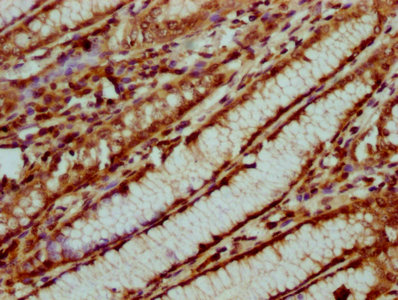

IHC image of CSB-PA010429OA31nsucHU diluted at 1:20 and staining in paraffin-embedded human gastric cancer performed on a Leica BondTM system. After dewaxing and hydration, antigen retrieval was mediated by high pressure in a citrate buffer (pH 6.0). Section was blocked with 10% normal goat serum 30min at RT. Then primary antibody (1% BSA) was incubated at 4°C overnight. The primary is detected by a biotinylated secondary antibody and visualized using an HRP conjugated SP system.

IHC image of CSB-PA010429OA31nsucHU diluted at 1:20 and staining in paraffin-embedded human pancreatic cancer performed on a Leica BondTM system. After dewaxing and hydration, antigen retrieval was mediated by high pressure in a citrate buffer (pH 6.0). Section was blocked with 10% normal goat serum 30min at RT. Then primary antibody (1% BSA) was incubated at 4°C overnight. The primary is detected by a biotinylated secondary antibody and visualized using an HRP conjugated SP system.